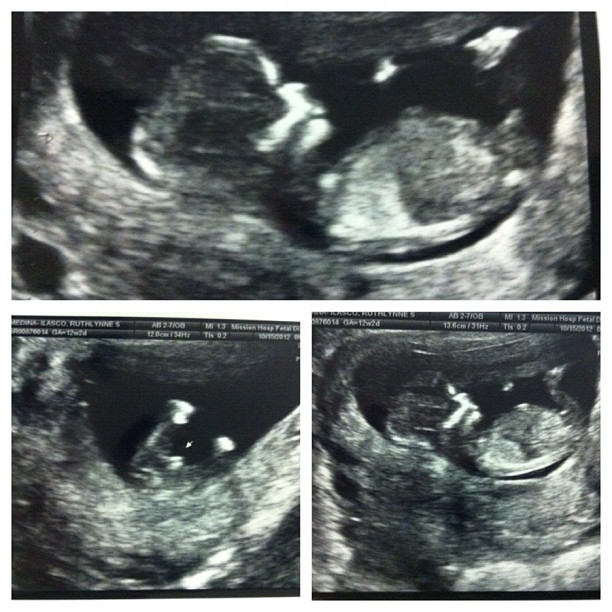

Doctors are 90% sure it’s a boy. Even at 12wks. See how “its” peeking out? ππ we’ll know for sure in another month but we’re happy right now that baby is healthy despite mommy being sick with the flu and cough. :)) ππ Rinnah was so happy she saw her “bro” for the first time. Now she keeps on rubbing my belly talking to baby. ππ:)) (Taken with Instagram)